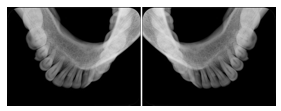

2. A patient requests cosmetic surgery to enhance their facial appearance. The case requires consultation between an orthodontist in New York and an oral surgeon in California. The cephalometric series of 2D projections constructed from the volumetric CT data that is used for the discussion is arranged by a Structured Display for transfer between the two practitioners.

Cephalometric Series Structured Display

Figure OO-2. Cephalometric Series Structured Display